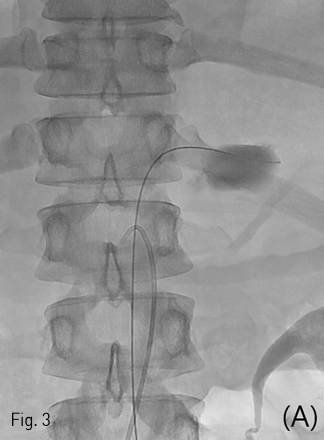

Cobra catheter로 교체하여 상위장간막동맥 조영술을 시행하였을 때 상위장간막동맥의 혈류는 원활하였음. 카테터를 상위장간막동맥 입구에 거치한 상태로 왼쪽 온넙다리동맥을 천자하여 6Fr sheath를 거치하고 guidewire를 이용하여 진입시킬 때 대동맥 손상 부분을 통해 guidewire가 나가는 것이 확인됨 (Fig. 3A). 이 때 guidewire 부분이 반드시 스텐트-그래프트로 덮어야 할 부분이고, 카테터가 있는 부분이 반드시 스텐트-그래프트로 덮지 말아야 할 부분이라 할 수 있음. 이후 왼쪽 온넙다리동맥 천자부위를 Preclose technique으로 16Fr sheath로 교체하고 (Fig. 3B) Gore excluder aortic extender 23 mm x 3.3 cm를 성공적으로 설치하였음(Fig. 3C).

Fig 3A

(A) A 0.035-inch guidewire and a 5 Fr Cobra catheter were located in lumen of ruptured pseudoaneurysm (must be covered) and os of superior mesenteric artery (should never be covered), respectively.